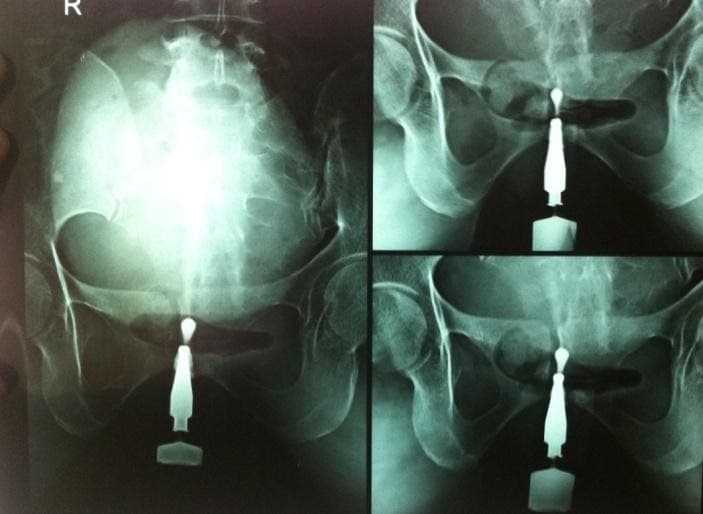

5. Micturating / Voiding Cystourethrogram (MCUG/VCUG)

A radiological investigation in which the bladder is filled with a radio-opaque dye using a small tube and x-ray snaps are taken while the patient passes urine.